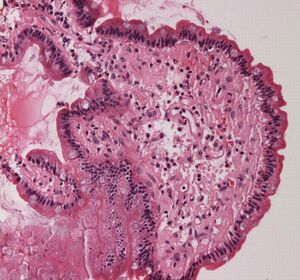

Micrograph showing amyloid deposits (pink) in small bowel. Duodenum with amyloid deposition in lamina propria. Amyloid shows up as homogeneous pink material in lamina propria and around blood vessels. 20× magnification.